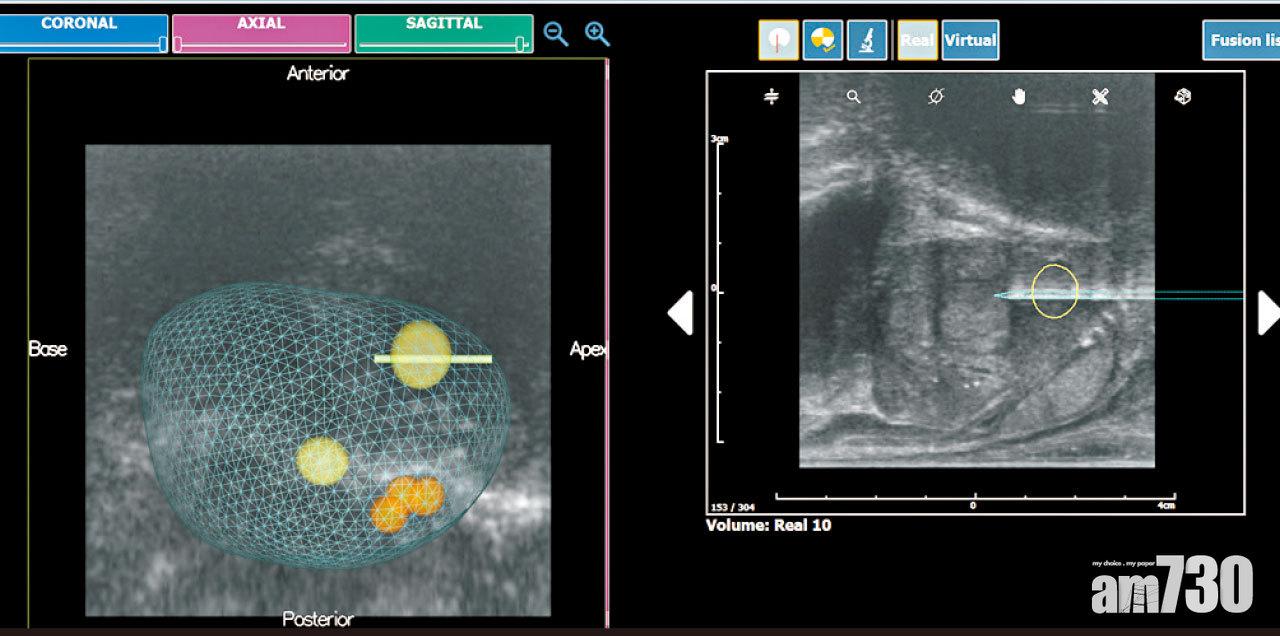

③ 最新的磁力共振超聲波影像融合技術。將磁力共振影像輸入超聲波儀器,透過最新的影像融合技術(MRI/USG fusion),當醫生抽針活檢時,所顯示出來的影像,已經融合了磁力共振及即時的超聲波影像,即使病人在活檢時體位改變,亦可以修正前列腺變形的誤差,從而令活檢的準確度進一步提高。

磁力共振超聲波融合技術(圖左),令醫生可更準確掌握前列腺懷疑腫瘤位置(黃色部分),以便針對性地落針(綠色)。